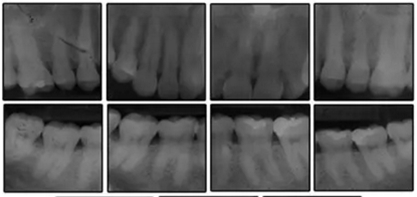

患者是一名39歲的白人婦女,病史不明。她主訴是她的右側(cè)顳下關(guān)節(jié)有不適癥狀,并希望改善她的笑容。她有一個(gè)對(duì)稱的臉型和一個(gè)II類2分類的微笑。她的側(cè)貌是凸的,90°的鼻唇角和骨性下頜骨發(fā)育不足??趦?nèi),上頜中線與面部重合,但下頜中線向右側(cè)偏移5mm;存在6mm的深覆蓋。她的兩側(cè)都是I類磨牙關(guān)系,左側(cè)是I類尖牙關(guān)系,右側(cè)是完全的II類尖牙關(guān)系。下頜右側(cè)第二前磨牙先天性缺失(圖1和圖2)。最初的全景片顯示了足夠的骨質(zhì)水平和全部的第三磨牙(圖3)。治療前的頭影測(cè)量片片和相應(yīng)的頭影測(cè)量圖(圖3)證實(shí)ANB為7°,Wits評(píng)估為6 mm的骨性II類錯(cuò)合(表)。上頜切牙相對(duì)與面部和顱底的位置很好。下頜切牙前傾。診斷為II類2分類錯(cuò)合畸形,伴有骨性下頜發(fā)育不足,右側(cè)顳下頜關(guān)節(jié)癥狀,下頜中線向右側(cè)偏移5mm,先天性右下第二前磨牙缺失。

圖3. 治療前頭影側(cè)位片,頭影測(cè)量描跡圖和全口X光片

患者決定采用非手術(shù)治療方法,側(cè)貌沒(méi)有任何預(yù)期的變化。治療后面部照片(圖5)顯示她改善的微笑和側(cè)貌,包括尖牙保護(hù)合。由于先天性第一前磨牙缺失,右磨牙關(guān)系為III類。治療后牙齒石膏模型(圖6)顯示實(shí)體牙齒交錯(cuò)排列情況,并且全景X線片顯示可接受的牙根平行度而且沒(méi)有牙根吸收表現(xiàn)(圖7)。最終的頭影測(cè)量片(圖7)證實(shí)了面部評(píng)估,并且描跡圖顯示深覆蓋的改善,同時(shí)保持上頜切牙位置并通過(guò)測(cè)量ANB角度和Wits評(píng)估改善骨性II級(jí)關(guān)系(表)。治療前后的疊加圖顯示由于下頜切牙前傾的增加改善了下唇平衡(圖8)。如相關(guān)治療計(jì)劃所預(yù)測(cè)的那樣,B點(diǎn)出現(xiàn)。A進(jìn)行牙科錐形束計(jì)算機(jī)斷層掃描以記錄下頜前牙區(qū)的骨質(zhì)變化。如預(yù)期的那樣,由于治療導(dǎo)致該區(qū)域的骨量增加(圖9)。